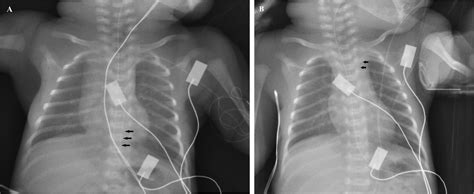

• Imaging Tests: Imaging tests such as MRI or CT scans may be used to visualize the brain and spinal cord for any abnormalities.

• Neuroimaging Studies: Advanced neuroimaging techniques can provide insights into the brain and spinal cord abnormalities that contribute to the condition.